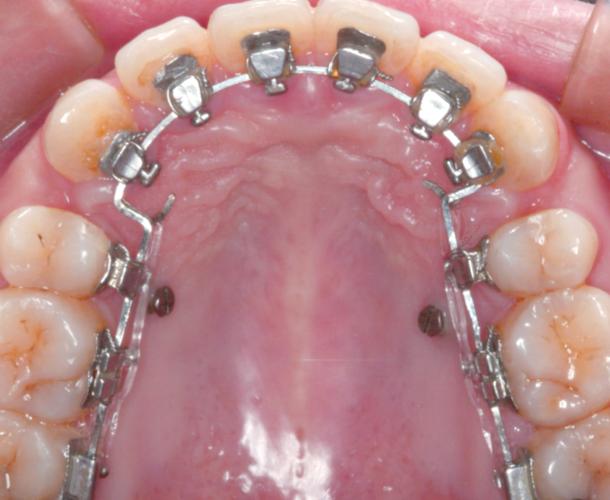

颌内牵引是指在同一牙弓内,通过牵引装置(如橡皮圈、螺旋弹簧、链状圈等)作用于单个或多个牙齿,实现牙齿的近远中移动、压低、伸长或扭转纠正,其图片特征主要包括:

- 牵引装置特写:口内直视图片中可见牙齿上粘贴的托槽、颊面管,以及连接于其间的橡皮圈(通常为“⟂”形或“8”形)或金属弹簧,例如使用镍钛螺旋弹簧关闭拔牙间隙时,图片中可清晰显示弹簧的压缩状态及两端与托槽的固定情况;

- 牙根与牙槽骨变化:通过根尖片或曲面断层片,可观察牙根是否平行、牙槽骨骨密度是否均匀,例如压低磨牙时,根尖片需显示牙根周围无骨吸收、牙槽嵴高度稳定。